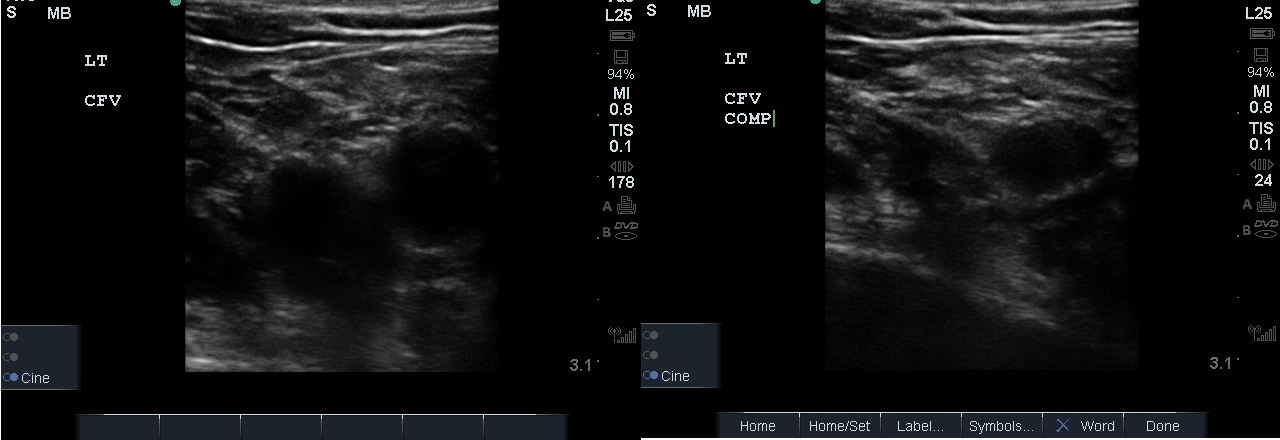

- Identify the inguinal crease at the very proximal medial thigh and place the transducer in a transverse orientation as indicated in Fig. 8. You should see the CFA and CFV as in the corresponding ultrasound image. If you see three vessels (CFA, CFV, SV), you are not proximal enough. Compress the CFV (Fig. 8 and 9).

- Figure 8. Common femoral vein and artery at the inguinal crease with transducer orientation indicated (red rectangle)

- Figure 9. Compression of the common femoral vein at the level of inguinal crease.